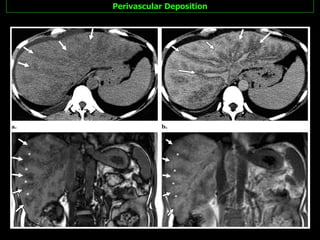

Perivascular Deposition This pattern is characterized by halos of fat that surround the hepatic veins, the portal veins, or both hepatic and portal veins.  The configuration is  tramlike  or tubular for vessels with a course in the imaging plane and  ringlike  or round for vessels with a course perpendicular to the imaging plane.

Perivascular Deposition An unequivocal signal  intensity loss on opposed-phase images  in comparison with that on in-phase images. The  lack of a mass effect  on the surrounded vessels are.  Indicative of the diagnosis The pathogenesis of perivascular fat deposition in the liver is unknown.

Perivascular Deposition

Perivascular Deposition Thispattern is characterized by halos of fat that surround the hepatic veins, the portal veins, or both hepatic and portal veins. The configuration is tramlike or tubular for vessels with a course in the imaging plane and ringlike or round for vessels with a course perpendicular to the imaging plane.

Perivascular Deposition Anunequivocal signal intensity loss on opposed-phase images in comparison with that on in-phase images. The lack of a mass effect on the surrounded vessels are. Indicative of the diagnosis The pathogenesis of perivascular fat deposition in the liver is unknown.